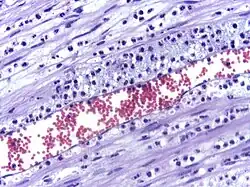

Micrograph showing leukocyte migration, H&E stain